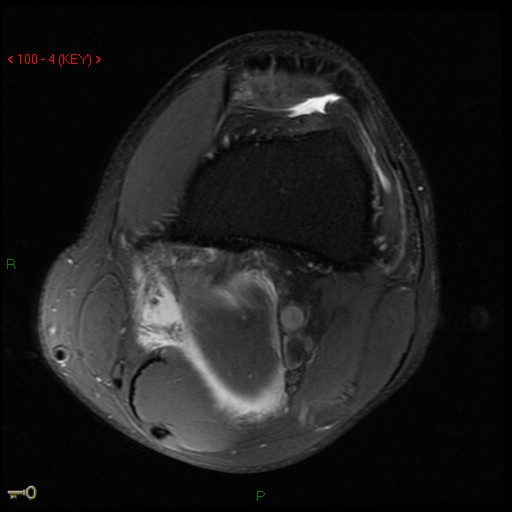

Figure 3 for case Medial head of gastrocnemius muscle ( RID2921 ) avulsion

Figure 3